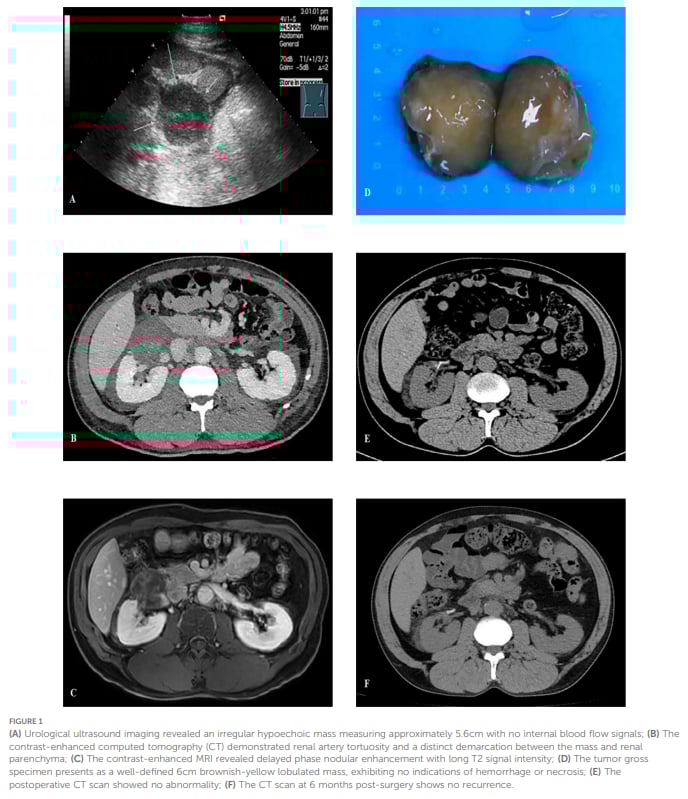

当患者因体检或症状发现肾周肿块时,通常会进行超声、CT或MRI等影像学检查。然而,PMPF在影像学上表现多样,有时边界清晰,有时又可能出现不规则强化,这些特征与一些恶性肿瘤(如肾细胞癌、脂肪肉瘤)的影像学表现存在重叠。例如,本案例中的患者,最初的超声和CT检查提示右肾下内侧存在肿块,增强MRI甚至显示为Bosniak IV型复杂囊肿,这在临床上往往意味着高度怀疑恶性病变。仅仅依靠影像学,很难给出明确的良恶性判断。

本文报道的中国首例肾周脂肪黏液性假瘤病例,充分展现了基因检测在精准诊断中的决定性作用。这名54岁男性患者,因右肾下内侧肿块入院,影像学检查提示复杂性囊肿,无法排除恶性。手术切除后,初步病理检查显示部分细胞存在异型性,免疫组化MDM2呈阳性,初步考虑为高分化脂肪肉瘤。

面对这一结果,患者和家属无疑承受着巨大的心理压力。然而,后续的基因检测结果却“拨乱反正”:MDM2基因、CDK4基因无扩增,DDIT3基因无断裂。这一结果与初步诊断明显不符。经过上级肿瘤专科医院的病理会诊和基因检测复核,最终结合所有证据,明确诊断为肾周脂肪黏液性假瘤。术后6个月的随访显示患者临床疗效良好,无复发迹象。这个案例不仅填补了中国PMPF病例报告的空白,更以实际行动证明了基因检测在鉴别诊断这种罕见病变中的不可替代性。

▲图1 影像学和手术标本结果